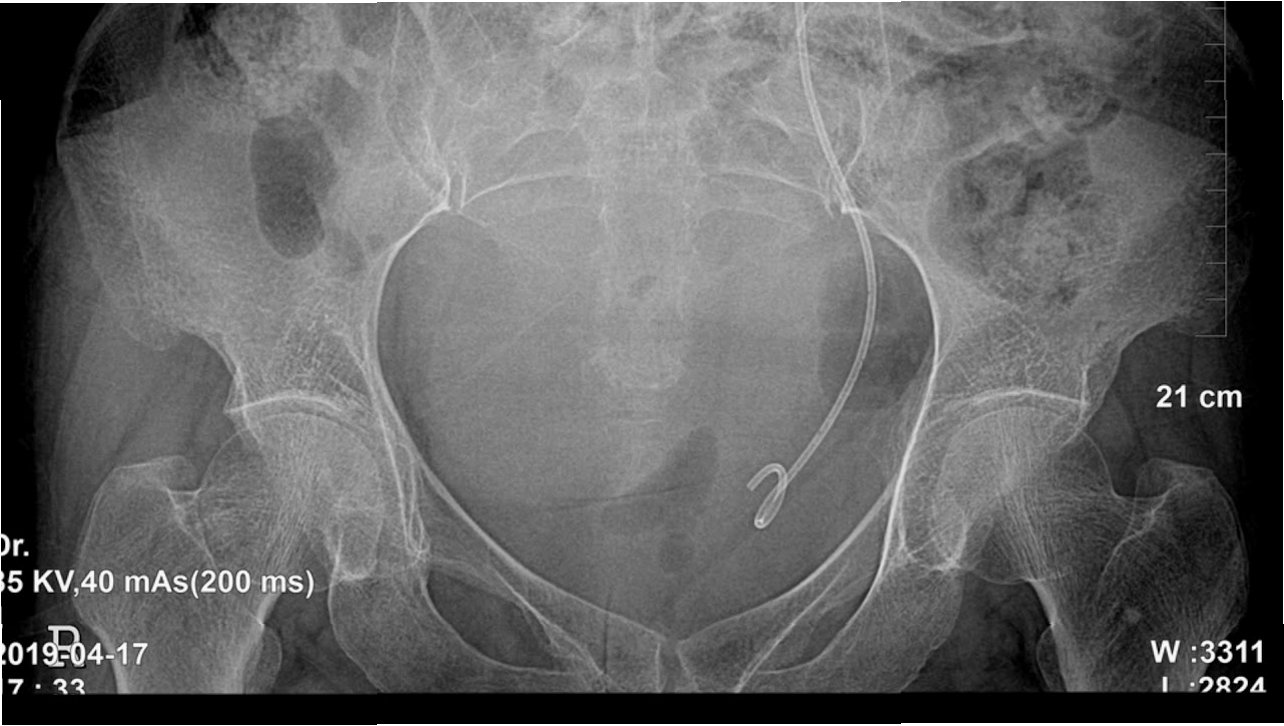

요로결석 수술을 결정하기 전에, 정확한 진단과 평가가 필수적입니다. 먼저, 환자의 병력 청취와 신체 검사를 통해 결석의 위치와 크기, 그리고 환자의 건강 상태를 파악합니다. 소변 검사, 혈액 검사, 영상 검사(X-ray, CT) 등을 통해 결석의 종류와 요로계의 해부학적 구조를 확인합니다. 이러한 검사 결과를 바탕으로, 환자에게 가장 적합한 수술 방법을 결정하게 됩니다. 수술 전에는 금식, 혈압 조절 등 수술에 필요한 기본적인 준비가 이루어집니다.

2. 요관 내시경 수술(URS): 요도, 방광을 거쳐 요관 내시경을 삽입하여 결석을 직접 제거하거나 레이저로 분쇄하는 방법입니다. 결석의 위치에 관계없이 비교적 효과적으로 결석을 제거할 수 있으며, 빠른 회복을 기대할 수 있습니다.